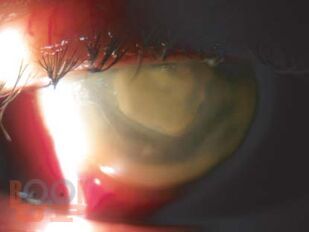

Семиотика и дифференциальная диагностика воспалительных заболеваний роговицы

Представлена характеристика ведущих симптомов и типичные внешние проявления различных нозологических форм паннусов, кератитов, язв роговицы.